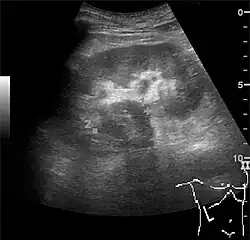

One of the primary indications for referral to US evaluation of the kidneys is evaluation of the urinary collecting system. Enlargement of the urinary collecting system is usually related to urinary obstruction and can include the pelvis, the calyces and the ureter. Hydronephrosis is seen as an anechoic fluid-filled interconnected space with enhancement within the renal sinus, and normally, the dilated pelvis can be differentiated from the dilated calyces.[1]

Figure 13. Hydronephrosis due to ureteropelvic junction obstruction in a pediatric patient.[1]

Several conditions can result in urinary obstruction. In both adults and children, masses, such as abscesses and tumors, can compress the ureter. In children, hydronephrosis can be caused by ureteropelvic junction obstruction, ectopic inserted ureter, primary megaureter and posterior urethral valve (Figure 13). In the latter, both kidneys will be affected. In adults, hydronephrosis can be caused by urolithiasis, obstructing the outlet of the renal pelvis or the ureter, and compression of the ureter from, e.g., pregnancy and retroperitoneal fibrosis. Urolithiasis is the most common cause of hydronephrosis in the adult patient and has a prevalence of 10%–15%.[1]